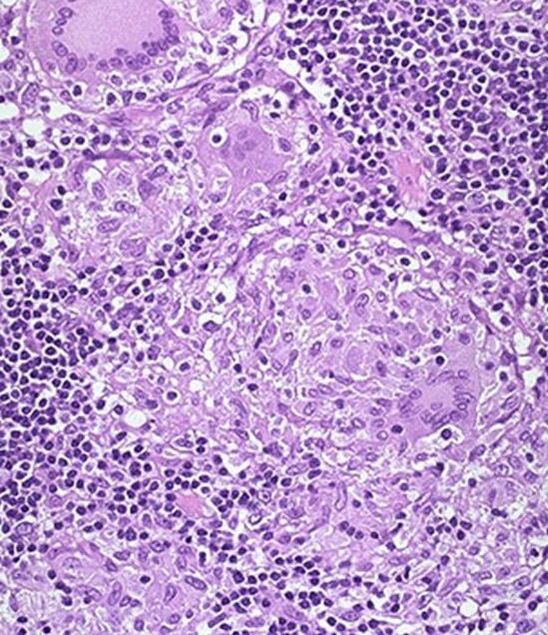

Микроскопически во всей толще кишки воспалительный инфильтрат, состоящий из лимфоцитов, плазматических клеток, эозинофилов. Образуются характерные гранулёмы из эпителиоидных клеток и гигантских многоядерных клеток типа Пирогова-Лангханса. Творожистый некроз в гранулёмах не наблюдается, что сближает их с саркоидозными гранулёмами.

Для болезни Крона характерно поражение лимфатических узлов, в них лимфомакрофагальная гиперплазия и эпителиоидные гранулёмы.